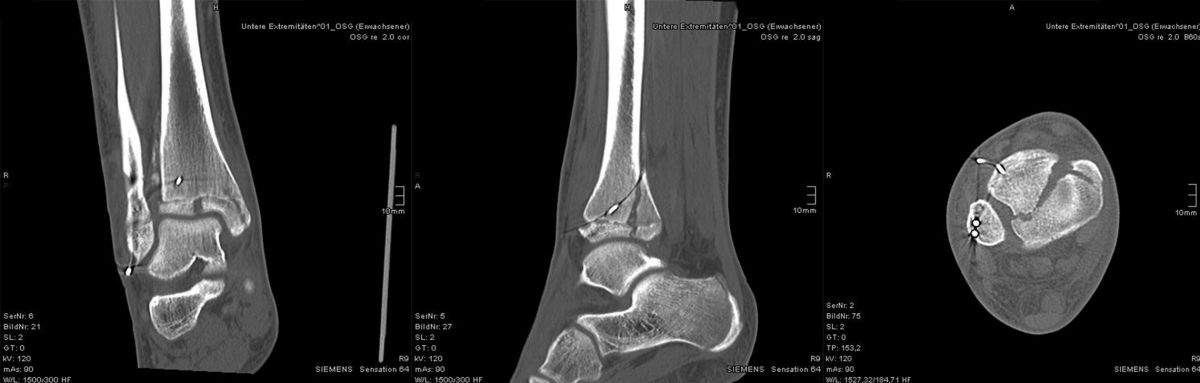

Der teilweise komplexe Frakturverlauf bei Übergangsfrakturen lässt sich im CT zuverlässig darstellen 10. Der erfahrene Untersucher kann bereits mit Röntgenaufnahmen des Sprunggelenks in zwei Ebenen in Verbindung mit zwei 45° Schrägaufnahmen sehr umfassende Aussagen zum Frakturverlauf treffen (v. Laer 2013), die Präzision und Aussagekraft der Computertomografie ist aber zweifelsohne überlegen und wird von den meisten Behandlern bevorzugt 11, auch wenn sich zu diesem Thema in der Literatur eine teilweise sehr emotional geführte Diskussion findet. Einigkeit hinsichtlich der Indikation für ein Schnittbildverfahren besteht bei Triplane-Frakturen, wenn Zweifel darüber bestehen, inwieweit die metaphysäre Fraktur den tragenden Gelenkanteil tangiert 12.

Dislozierte Frakturen (Frakturspalt > 2 mm) werden grundsätzlich operativ behandelt. Die Reposition kann arthroskopisch unterstützt erfolgen. Die Schraubenosteosynthese erfolgt entsprechend dem Frakturverlauf. Bei Twoplain Frakturen ist meist eine epiphysäre Schraube ausreichend die von lateral kommend das Fragment nach medial-proximal fixiert. Der Schraubenverlauf ist üblicherweise von lateral ventral nach proximal dorsal medial (Abb. 24). Nach Reposition darf in der seitlichen Aufnahme des Sprunggelenks, als auch in der 45° Außenrotationsaufnahme keine Stufe in Höhe der Wachstumsfuge erkennbar sein. Eine sichtbare Stufe ist Indikator für eine unzureichende Reposition.

Bei Triplane-Frakturen fasst die metaphysäre Schraube das metaphysäre Fragment einschließlich eines hinteren Volkmann Dreiecks, die epiphysäre Schraube fasst das epiphysäre Fragment. Da der Fugenschluss noch nicht abgeschlossen ist, sollten die Schrauben die Wachstumsfuge nicht kreuzen, obwohl eine Wachstumsstörung unwahrscheinlich ist (v. Laer 2013).